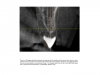

Fig. 27 through Fig. 30 The radiograph shows a periapical radiolucency. Three slices from the CBCT show a clear root fracture and buccal fistula showing an unrestorable tooth. With the CBCT information, the doctor can explain alternatives to the patient and not be surprised at the time of surgery.

Figure 27

Figure 28

Figure 30